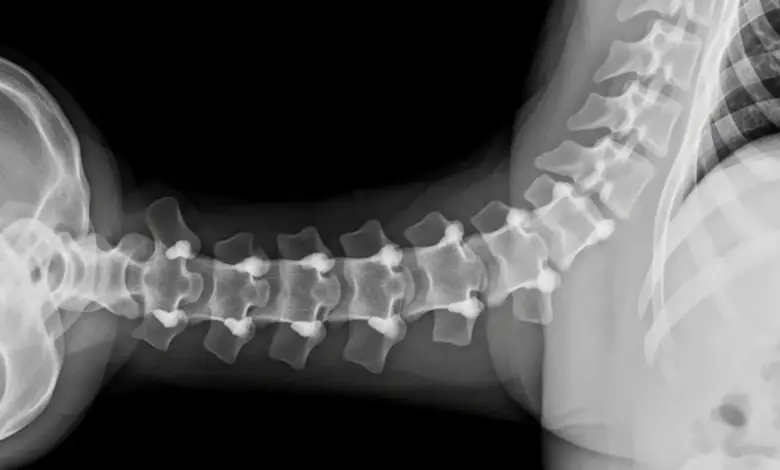

Exames de imagem ajudam a mapear a extensão do desgaste e excluir outras causas de dor, como hérnias.

- Radiografia para avaliar alinhamento e sinais de artrose.

- Ressonância magnética para analisar cartilagem, cápsula e tecidos moles.

- Tomografia quando há dúvida estrutural óssea.